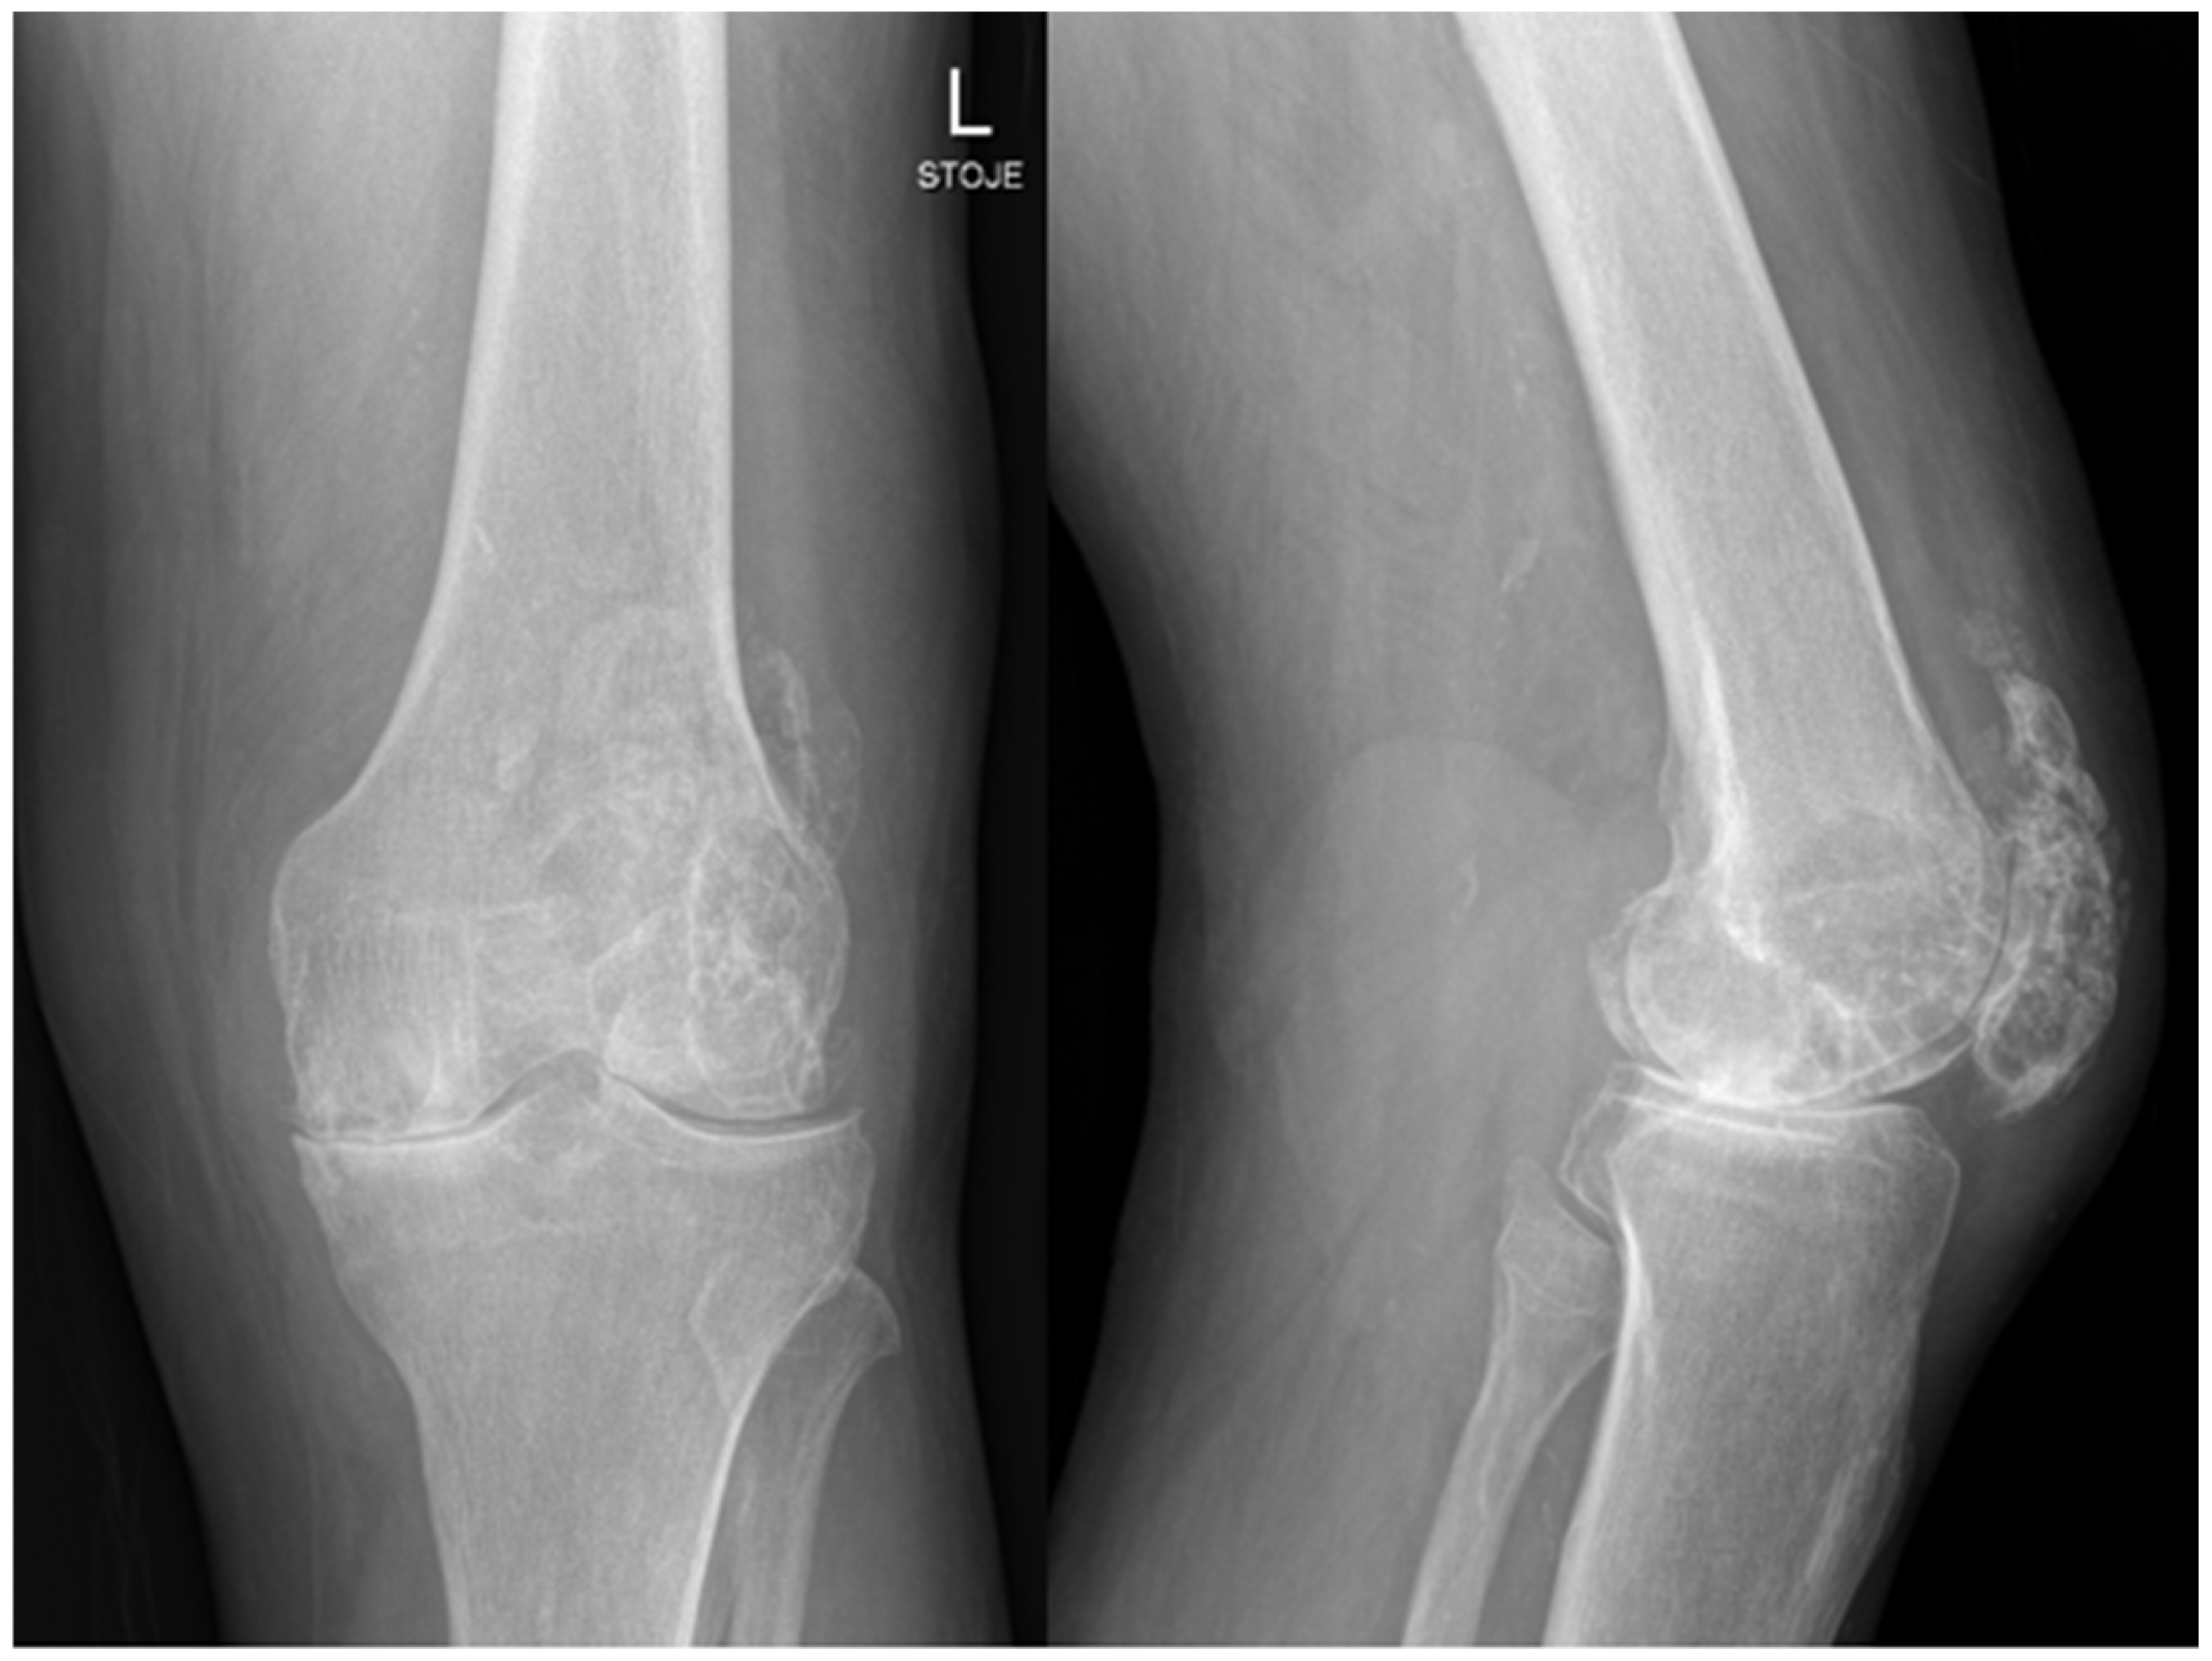

A 71-year-old man with prostate cancer on hormonal therapy, chronic heart disease, hypertension, and hyperlipidemia underwent a primary left knee arthroplasty due to secondary post-traumatic osteoarthritis in February 2024. The patient had a knee arthroscopy in 2012 and reconstruction of the quadriceps tendon in 2014 on the same knee. The primary knee replacement was performed in February 2024 and was particularly challenging because of a large degenerative cyst in the lateral femoral condyle and a weakened quadriceps tendon with multiple foci of ossification. Preoperative severe osteoarthrosis of the left knee is presented on radiography in Figure 1.

Figure 1. Radiology of left knee—anteroposterior and lateral views of the knee before implantation of total knee endoprosthesis, showing severe knee osteoarthrosis with heterotopic ossifications after quadriceps rupture and surgical treatment years ago.